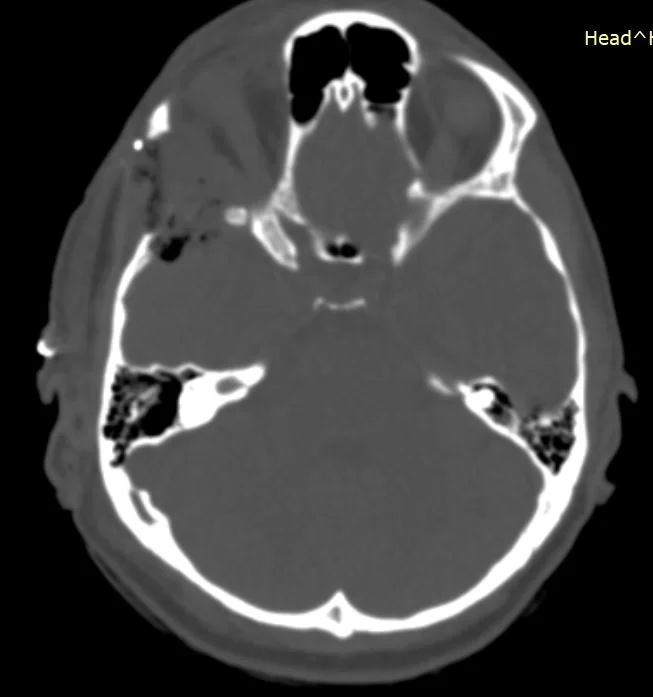

H Μαγνητική  & Αξονική Τομογραφία εγκεφάλου ανέδειξε χωροκατακτητική εξεργασία στην περιοχή της πτέρυγας του σφηνοειδούς οστού, δηλ. του άνω (οροφή) και του πλαγίου τοιχώματος του οφθαλμικού κόγχου. Η εξεργασία επεκτείνονταν κατά μήκος της σκληράς μήνιγγας ενώ στην περιοχή του κροταφικού πόλου παρουσίασε ενδοκρανιακή επέκταση. Η πάχυνση του οστού του κόγχου προκαλούσε πίεση των περιεχομένων του κόγχου με αποτέλεσμα εξόφθαλμο.

Η μετεγχειρητική αξονική τομογραφία εγκεφάλου ανέδειξε τη γενναιόδωρη αποσυμπίεση του κόγχου.